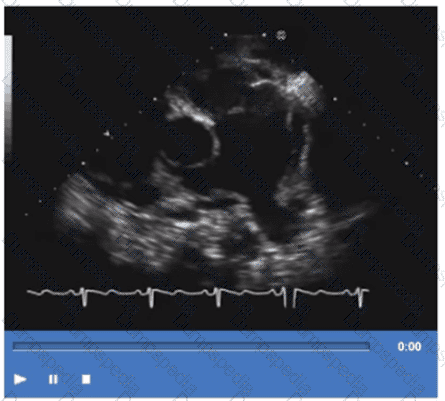

Which congenital abnormality is most consistent with the findings in this video?